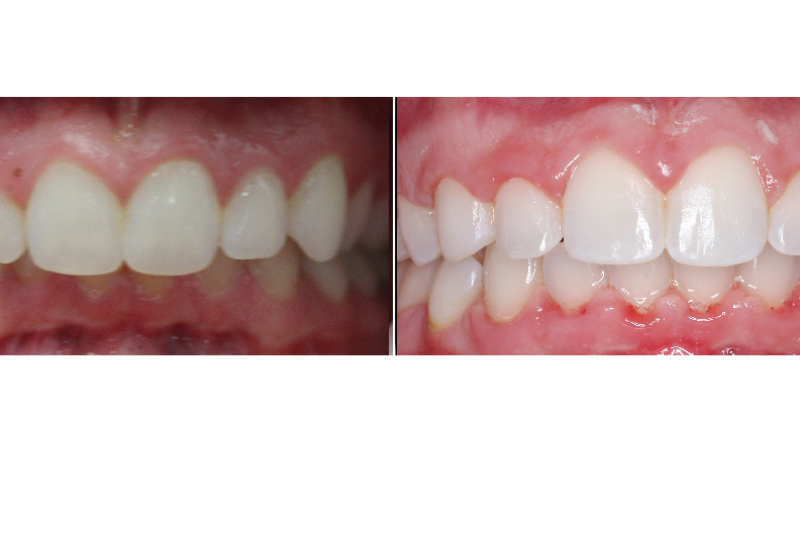

Been doing this for 19y, but I’m still amazed how my work can change a person’s look/life in just a year!